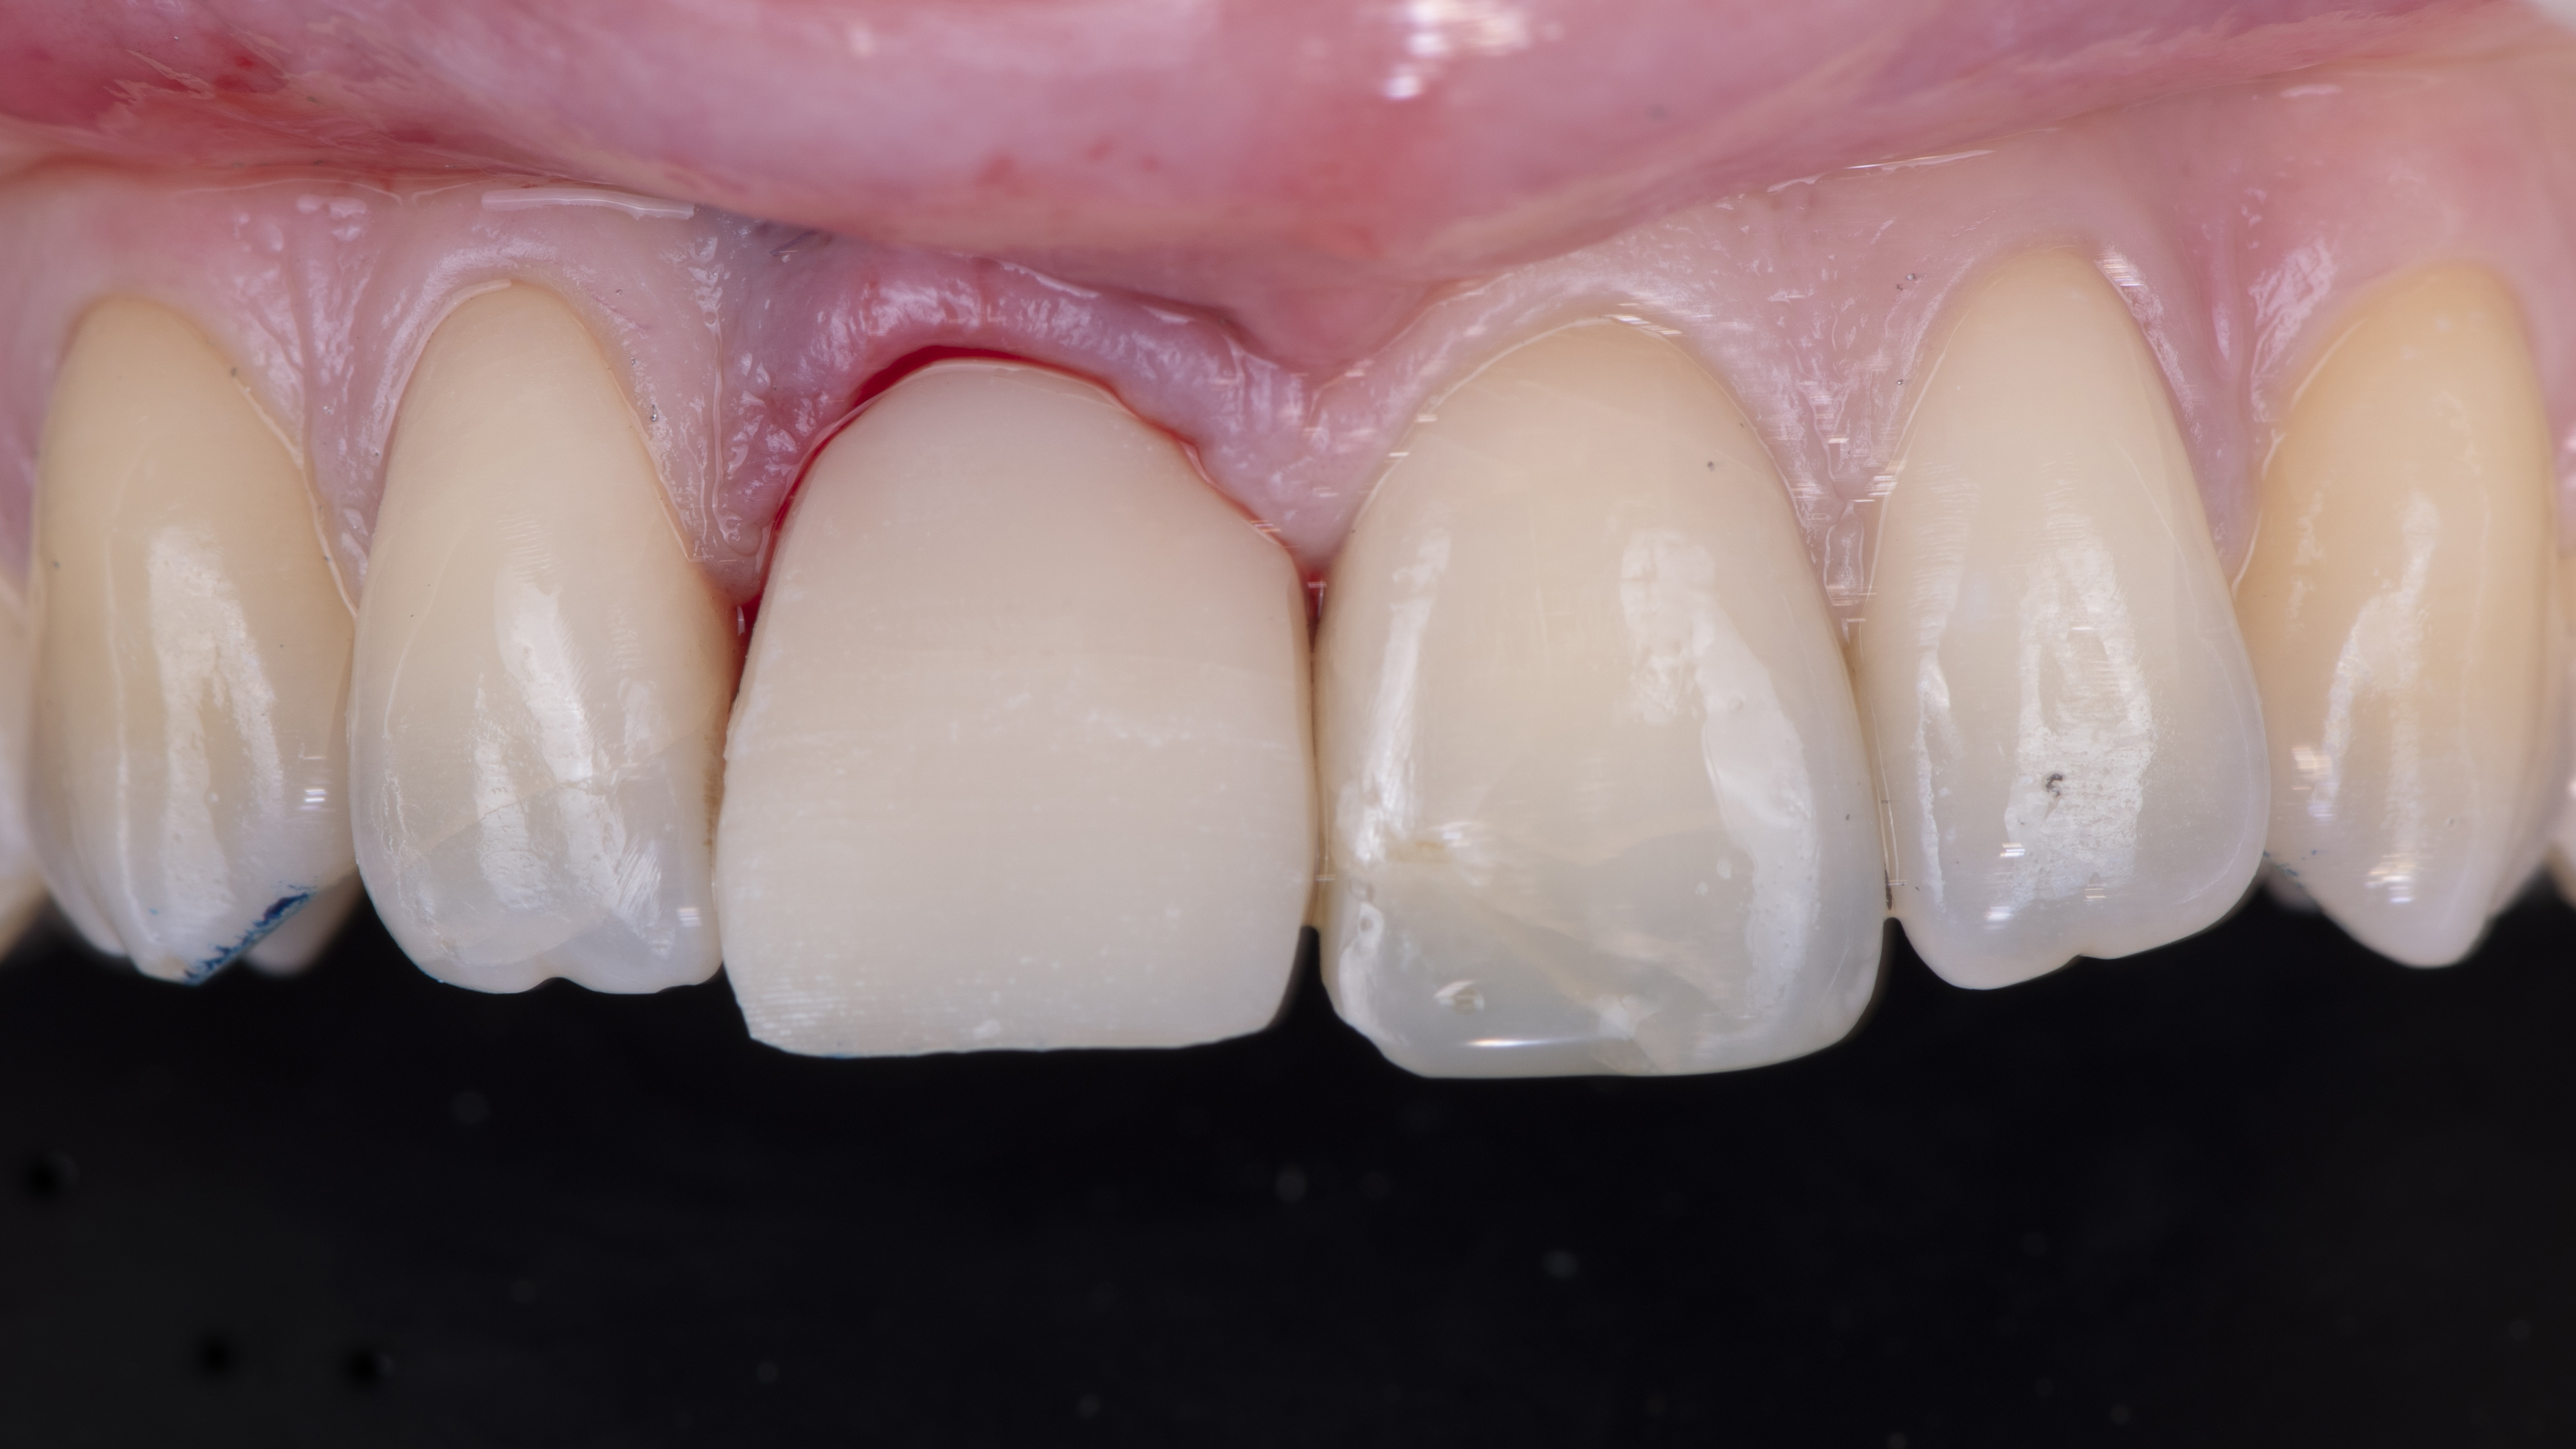

Une copie de la couronne de la patiente est imprimée et évidée pour permettre de la positionner correctement. Elle est ensuite solidarisée à un pilier provisoire vissé dans l’implant. Ceci nous permet ensuite d’ajuster le profil d’émergence (Photo 12).

La couronne provisoire est ensuite repositionnée et les contacts en occlusions statique et dynamique sont supprimés pour éviter d’appliquer des forces sur l’implant pendant toute la période d’ostéointégration (Photo 15).